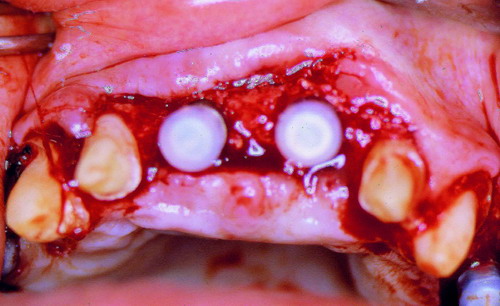

LA OCLUSIÓN MUTUAMENTE PROTEGIDA ES UN VIEJO CONCEPTO QUE CONSISTE EN LA MUTUA INTERACCIÓN DE LOS DISTINTOS GRUPOS DENTARIOS ENTRE SI. DE ESTA FORMA, LA TABLA PREMOLAR / MOLAR DE AMBOS HEMIMAXILARES ANTAGONISTAS, DETIENEN EL CIERRE MANDIBULAR EN CÉNTRICA, LOS CANINOS DISCLUYEN LAS PIEZAS POSTERIORES DURANTE LAS TRANSTRUSIONES, Y EL GRUPO INCISIVO LO MISMO DURANTE LAS PROPULSIVAS. SIN EMBARGO, DICHO CONCEPTO ES LIMITADO A LAS PIEZAS DENTARIAS, SIN TENER EN CONSIDERACIÓN LA IMPORTANTE FUNCIÓN QUE RECAE SOBRE LA ATM Y EN EL SOPORTE DE PRESIONES DURANTE ESTA DINÁMICA. ES ASI QUE EN EL AÑO 1981, EL DR. ANIBAL ALONSO GENERA EN LA CIUDAD DE BUENOS AIRES UN CONCEPTO MAS AMPLIO QUE DENOMINÓ : OCLUSION MUTUAMENTE COMPARTIDA. REF I EN EL QUE AMPLÍA EL CONCEPTO ANTERIOR, HACIENDO PARTÍCIPE A LA ATM EN LA MISMA. CUANDO EXISTE CARENCIA DE PIEZAS DENTARIAS POSTERIORES, YA SEA DE UN SOLO LADO O DE AMBOS , EL CIERRE MANDIBULAR ES DETENIDO POR LAS PIEZAS RESTANTE, FORZANDO A LA ATM A SOPORTAR PRESIONES MUY SUPERIORES A AQUELLAS PARA LAS QUE ESTA PREPARADA. FIG1 FIG2 FIG3 LUEGO DEL ESTUDIO CLÍNICO DE RIGOR, DONDE SE EVALÚA RADIOGRÁFICA Y PERIODONTALMENTE, SE PROCEDE A TOMAR MODELOS DE ESTUDIO Y MONTAR EN ARTICULADOR SEMIAJUSTABLE, SOBRE EL CUAL SE REALIZA UN ENCERADO PROGRESIVO DE DIAGNÓSTICO, A PARTIR DEL CUAL SE CONFECCIONA UN JUEGO COMPLETO DE PROVISIONALES DE AMBAS ARCADAS , INCLUYENDO LAS PIEZAS FALTANTES. SE ABORDA EL CASO YA QUIRÚRGICAMENTE DONDE EN UNA PRIMERA ETAPA SE TALLAN PRIMARIAMENTE LAS PIEZAS DENTARIAS Y SE PROCEDE, EXODONCIANDO EL INCISIVO CENTRAL SUPERIOR DERECHO, A REALIZAR UNA ROG(REGENERACIÓN ÓSEA GUIADA), PARA INMEDIATAMENTE INSTALAR PARTE DE NUESTROS PROVISORIOS EN LA GUIA ANTERIOR. SE ADAPTAN A LOS SECTORES POSTERIORES LAS PRÓTESIS REMOVIBLES QUE PORTABA, Y SE ESPERAN CUATRO MESES, AL CABO DE LOS CUALES SE REALIZA UN ESTUDIO CON DENTASCAN, MEDIANTE EL USO DE UNA FÉRULA RADIOLÓGICA CON TUBOS METÁLICOS , QUE NOS SERVIRÁ TAMBIÉN DE GUÍA QUIRÚRGICA. PROCEDEMOS ENTONCES A LA IMPLANTACIÓN DE LOS SECTORES EDÉNTULOS MEDIANTE IMPLANTES ROSCADOS Y TÉCNICA SEMI SUMERGIDA. TRANSCURRIDAS OCHO SEMANAS OBSERVAMOS UNA CORRECTA SALUD PERIMPLANTARIA, Y REALIZAMOS LA INSTALACIÓN DE LOS ABUTTMENTS ALCANZAMOS ENTONCES EL PUNTO EXACTO DONDE DEBEREMOS COMENZAR A RECONTRUIR EN FORMA PERMANENTE. PAZ DEL SISTEMA: CENTRICIDADARTICULAR-PAZ MUSCULAR-ESTABILIDAD- -ACOPLAMIENTO. BASES FUNDAMENTALES DE LA OCLUSIÓN ORGÁNICA FIG41 FIG42 PROCEDEMOS NUEVAMENTE A TOMAR IMPRESIONES, EN ESTE CASO DEFINITIVAS , MONTAR NUEVAMENTE EN ARTICULADOR, Y CONSTRUIR LAS RESTAURACIONES PERIFÉRICAS TOTALES EN BASE A PORCELANA SOBRE ORO GALVANIZADO. REF. II SOBRE LAS MISMAS TERMINADAS Y YA EN BOCA, CHEQUEÁMOS TODOS LOS ELEMENTOS QUE CONSTITUYEN UNA REHABILITACIÓN ORAL INTEGRAL, DESDE LA SALUD ENDODONTICA DE PIEZAS TRATADAS O NO, LA SALUD PERIODONTAL, EL AJUSTE PERIFÉRICO DE LAS RESTAURACIONES, LA ESTABILIDAD EN LA ATM, Y LAS FUNCIONES OCLUSALES, CHEQUEOS ESTOS QUE SE REPETIRAN EN CADA UNO DE LOS CONTROLES POST OPERATORIOS. FIG46 FIG47 FIG48 FIG66 FIG67 REFERENCIAS: REF I: OCLUSIÓN Y DIAGNÓSTICO EN REHABILITACIÓN ORAL REF. II ELECTROFORMACIÓN EN ODONTOLOGÍA RESTAURADORA.